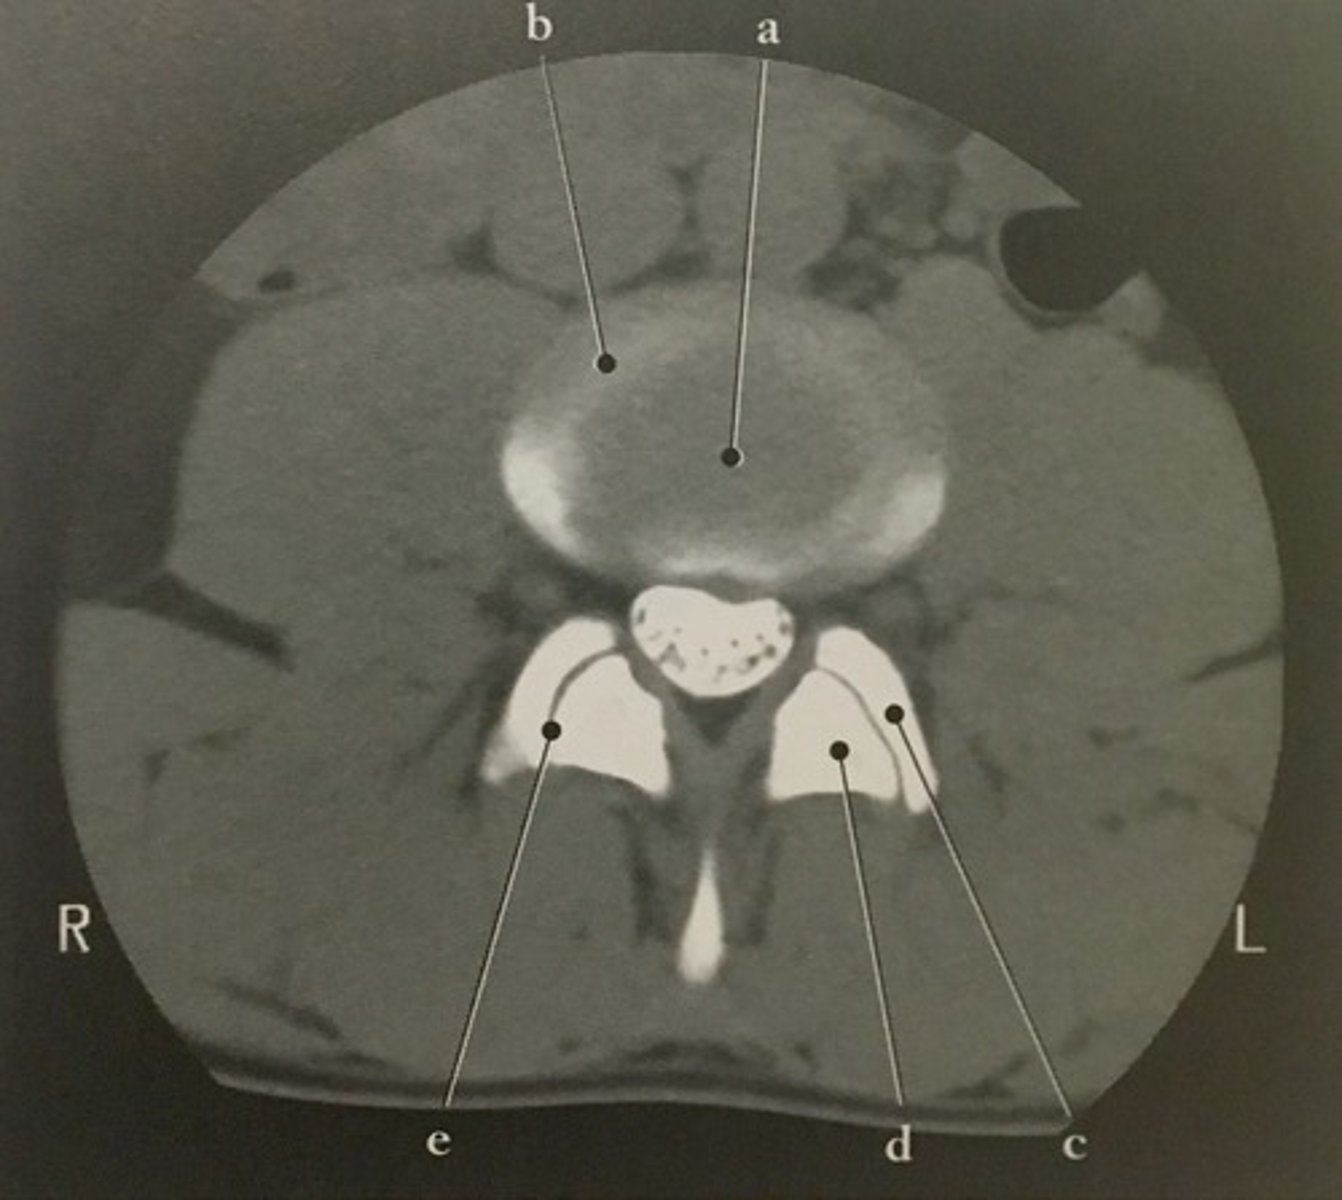

Body

Identify structure A on this axial CT slice of the lumbar vertebra.

<p>Identify structure A on this axial CT slice of the lumbar vertebra.</p>

Pedicle

Identify structure B on this axial CT slice of the lumbar vertebra.

<p>Identify structure B on this axial CT slice of the lumbar vertebra.</p>

Lamina

Identify structure C on this axial CT slice of the lumbar vertebra.

<p>Identify structure C on this axial CT slice of the lumbar vertebra.</p>

Transverse process

Identify structure D on this axial CT slice of the lumbar vertebra.

<p>Identify structure D on this axial CT slice of the lumbar vertebra.</p>

Posterior spinous process

Identify structure E on this axial CT slice of the lumbar vertebra.

<p>Identify structure E on this axial CT slice of the lumbar vertebra.</p>

Vertebral foramen

Identify structure F on this axial CT slice of the lumbar vertebra.

<p>Identify structure F on this axial CT slice of the lumbar vertebra.</p>